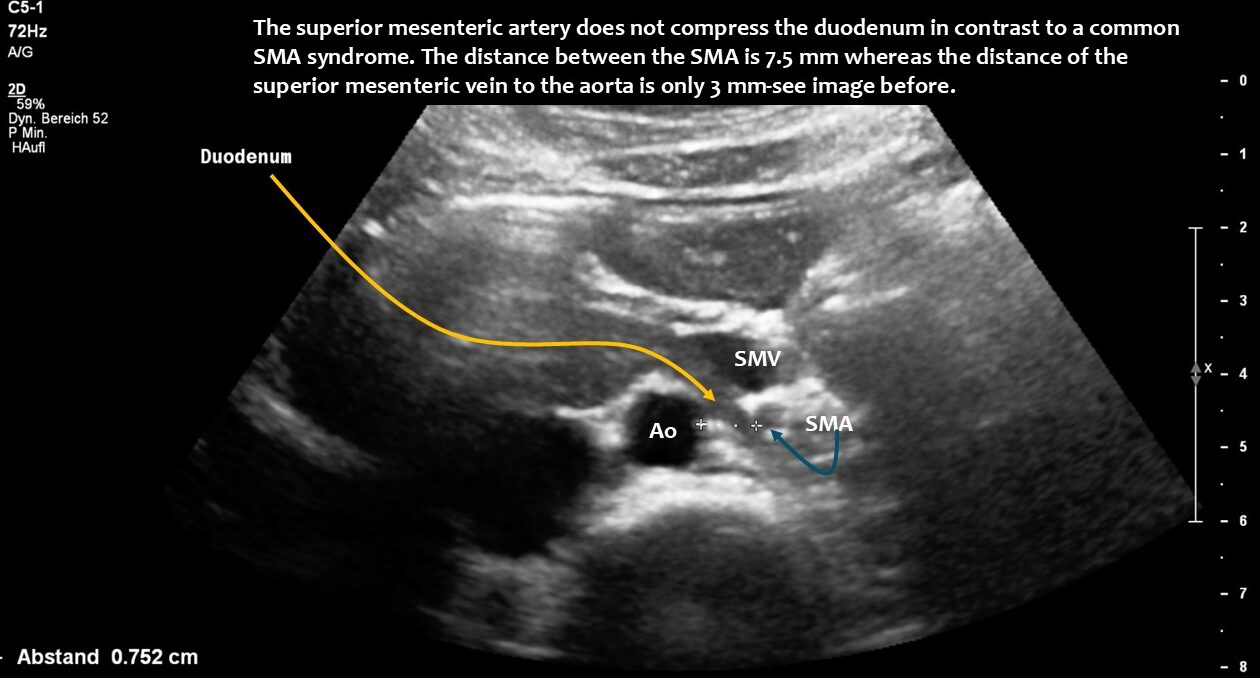

Here, the unique mechanism causing compression of the duodenum by the enlarged superior mesenteric vein is demonstrated. In contrast to conventional SMA syndrome, the superior mesenteric vein acts as a pillar against which the aorta presses, thus obstructing the duodenum. It is important to be aware of the variability in the position of the superior mesenteric artery in patients with a flat abdominal cavity. When the stomach is full, it may shift further to the left (or right) of the SMA than in the fasting position.

The volume of food ingested and the associated enlargement of the stomach now led to a critical situation: the stomach pushed the hepatic artery (arteria hepatica communis), which runs along the underside of the liver, against the portal vein (vena portae), which carries blood from the spleen and intestines to the liver. This compressed the portal vein and caused blood to accumulate in the splenic vein (Vena lienalis/Vena splenica) and, above all, in the superior mesenteric vein. While the splenic vein runs parallel to the pars horizontalis duodeni, the superior mesenteric vein cuts across the duodenum at a right angle, similar to the superior mesenteric artery. The congestion of the superior mesenteric vein led to compression of the duodenum, even though there was sufficient space between the superior mesenteric artery and the duodenum. However, after food intake, the superior mesenteric artery shifted far to the left and thus no longer formed a clamp with the aorta for the duodenum. The swelling of the superior mesenteric vein, which is supplied with significantly more blood after food intake than when fasting in order to transport food components to the liver, was so severe as a result of the compression of the portal vein that food could no longer pass through the pars horizontalis duodeni. The clinical consequences for the patient were increasing nausea after eating due to the considerable distension of the pars descendens duodeni, rapid satiety, impaired food transport from the stomach despite lively peristaltic contractions of the stomach (misinterpreted elsewhere as gastroparesis), vomiting and significant weight loss. Even feeding via a percutaneous jejunal tube and a gastric tube could not stop the weight loss.

Normal size of the superior mesenteric vein which is slightly slimmer than the superior mesenteric artery as long as the patient was fasting. However, due to the limited space in the flat upper abdomen the superior mesenteric artery already is shifted to the left side of the aorta instead of lying precisely in front of it.